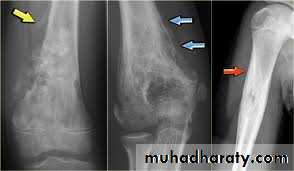

X-rays

variable hazy osteolytic .

areas may alternate with unusually dense Osteoblastic areas.The endosteal margin is poorly defined. often

The cortex is breached .

The tumour extends into the adjacent tissues; when this happens.

Streaks of new bone appear, radiating outwards from the cortex – the so-called ‘sunburst’ effect.Reactive new bone forms at the angles of periosteal elevation (Codman’s triangle).